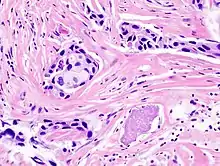

- Histopathology – the microscopic examination of stained tissue sections using histological techniques. The standard stains are haematoxylin and eosin, but many others exist. The use of haematoxylin and eosin-stained slides to provide specific diagnoses based on morphology is considered to be the core skill of anatomic pathology. The science of staining tissues sections is called histochemistry.

- Immunohistochemistry – the use of antibodies to detect the presence, abundance, and localization of specific proteins. This technique is critical to distinguishing between disorders with similar morphology, as well as characterizing the molecular properties of certain cancers.